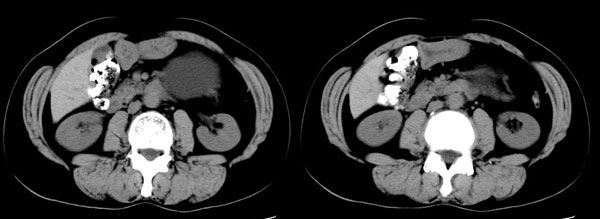

ct平扫加增强扫描:胆囊折叠,壁厚,其内见结石。胰腺体尾部见一5.8x7.5cm囊性肿物,ct值12hu,壁薄,增强扫描未明显强化,胰头不大,强化均匀。

ct诊断:1.胆囊炎,胆囊折叠并结石。

2.胰体尾部囊肿。